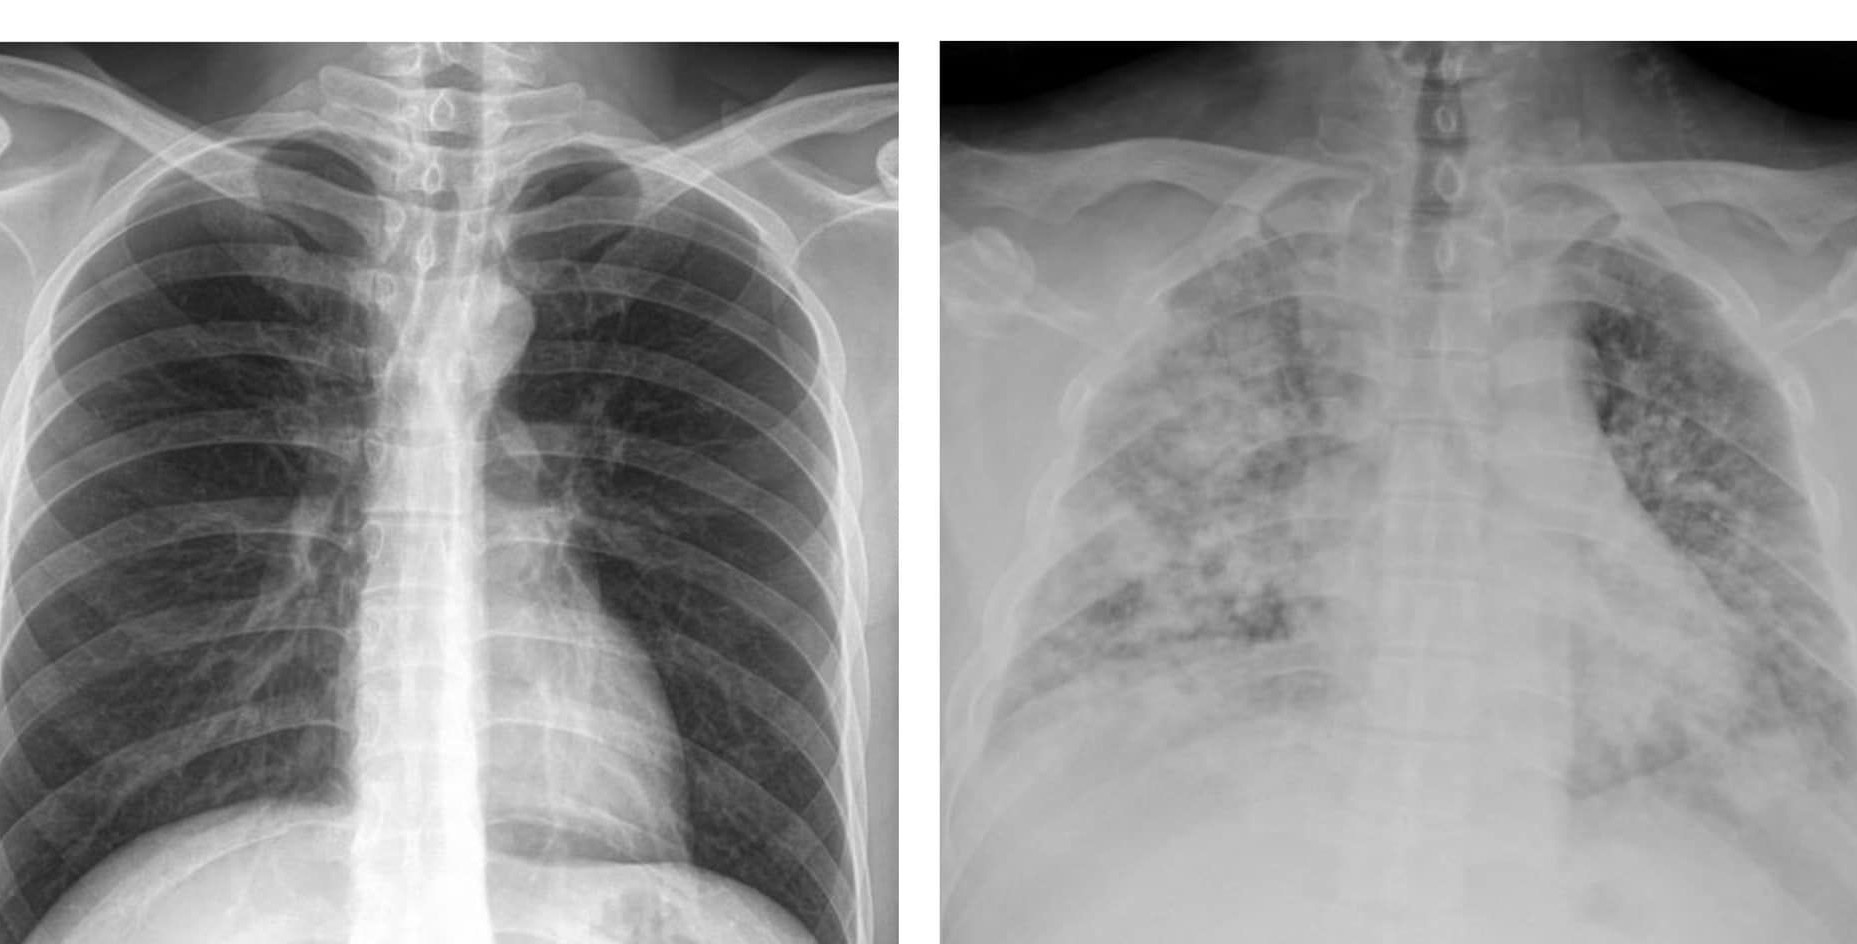

tu hy vien benh cum anh 3

Bác sĩ Đỗ Thành Triết đăng ảnh chụp X-quang phổi của một bệnh nhân bị viêm phổi nặng do cúm. Ảnh: ETtoday.